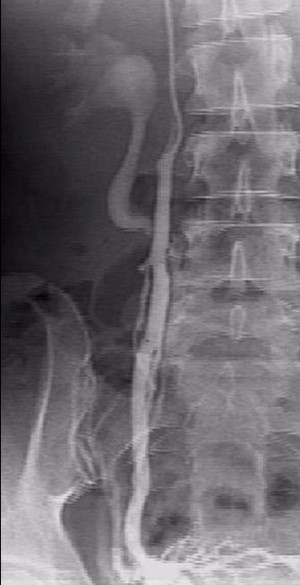

Примечательно, что абсолютно верную и точную информацию о наличии заболевания, состоянии вен малого таза на финальном этапе обследования помогает получить проведение инвазивного рентгеноконтрастного исследования. Во время селективной оварикографии и тазовой флебографии врачи уточняют анатомические особенности положения, строения яичниковых сосудов, их диаметр, выявляют количество и характер притоков гонадных сосудов, наличие рефлюкса, свойственного внутренним и яичниковым подвздошным венам, а также связь подкожных и сосудов малого таза.

После проведения единократного инвазивного внутрисосудистого исследования специалисты центра эндоваскулярной хирургии при терапии ВБВМТ применяют инновационный метод – эндоваскулярную эмболизацию гонадных сосудов.

Данная процедура предусматривает введение эмболизационных (закупоривающих) спиралей в вену через диагностический катетер, что позволяет полностью закупорить патологический кровоток. Операция не занимает много времени. При этом пациент может вернуться к привычной жизни уже в ближайшее время. Период реабилитации является несложным.